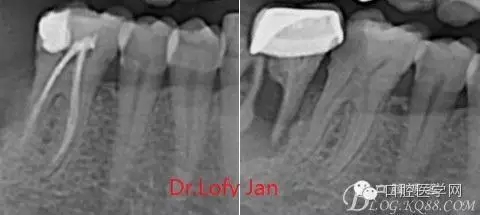

前言:自己做的一些曲面斷層片在未試尖根管治療中的病例整理,發(fā)現(xiàn)問題很多包括自身的,技術(shù)的,還有設(shè)備的問題,予以總結(jié)整理并期待進(jìn)一步提高。

根管治療術(shù)是牙體牙髓疾病治療中最復(fù)雜和最關(guān)鍵的治療項(xiàng)目。根管充填材料抵達(dá)根尖、并能嚴(yán)密堵塞根尖孔,是確保根管治療效果的關(guān)鍵指標(biāo)。為了保證根管充填到位,醫(yī)生需要在術(shù)前照牙片以了解牙根根管的數(shù)量、彎曲程度和長度,在術(shù)中有時(shí)需要插針照牙片來精確測量根管長度,術(shù)后必須照牙片以確定是否根管充填到位,如果欠填或超填,就需要重新充填、重新照牙片確認(rèn),直到根管充填到位。所以,在患者接受根管治療時(shí)有時(shí)會反復(fù)照牙片。

《數(shù)字化根尖片、曲面斷層片、CBCT測量牙齒長度準(zhǔn)確性的比較研究》文中顯示:平行投照數(shù)字化根尖片影像長度和牙齒實(shí)際長度之間無顯著性差異(P0.05);數(shù)字化曲面斷層片影像長度和牙齒實(shí)際長度之間有顯著性差異(P0.05),平均失真率為17.05%。CBCT冠狀面測量結(jié)果中除上頜前磨牙區(qū)、下頜前磨牙區(qū)與真實(shí)長度差異無統(tǒng)計(jì)學(xué)意義(P0.05)外,其余6個(gè)分區(qū)差異均有統(tǒng)計(jì)學(xué)意義(P0.05);矢狀面測量結(jié)果中上頜磨牙區(qū)、下頜磨牙區(qū)、下頜前磨牙區(qū)、下頜尖牙區(qū)、下頜前牙區(qū)與真實(shí)長度比較差異均有統(tǒng)計(jì)學(xué)意義(P0.05)。結(jié)論平行投照數(shù)字化根尖片較曲面斷層片和CBCT能更加精確地反映牙齒的真實(shí)長度。

病例分析:曲面斷層片在x線輔助診斷與檢查中目前大多數(shù)文獻(xiàn)和著作都建議只能作為初診拍片檢查手段,不能作為終末疾病的確診與手術(shù)療效的評價(jià)指標(biāo),臨床大部分中小型門診都因?yàn)樵O(shè)備不齊全導(dǎo)致信息偏差很大。